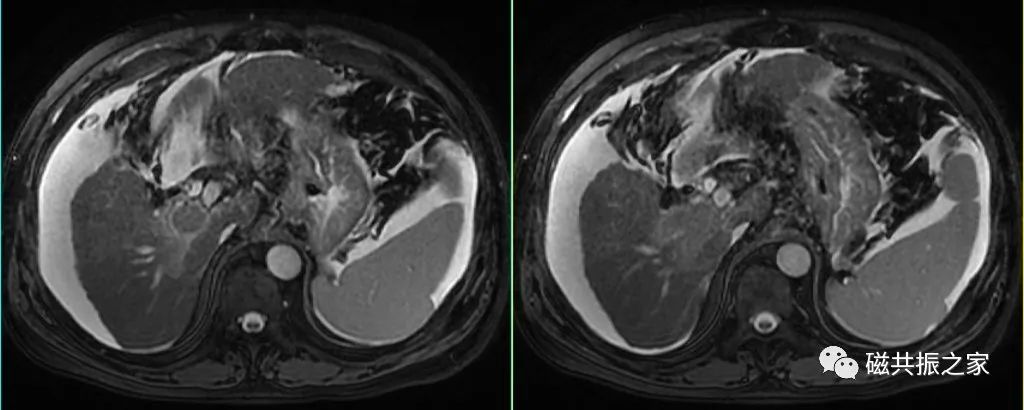

呼吸触发的横轴位T2WI脂肪抑制序列是上腹部扫描的“黄金序列”,做好该序列是关键,可结合如螺旋桨等技术来改善呼吸、血管搏动及胆囊蠕动的运动伪影。

对于呼吸不均,采用呼吸触发获得的图像质量较差时,可采用屏气的超长回波链-T2WI序列或单次激发T2WI序列或稳态自由进动序列替代扫描,但应注意替代序列对其病变的敏感性和特异性。

替代序列可采用快速的FSE或GRE序列,但应注意其对病变的敏感性和特异性。